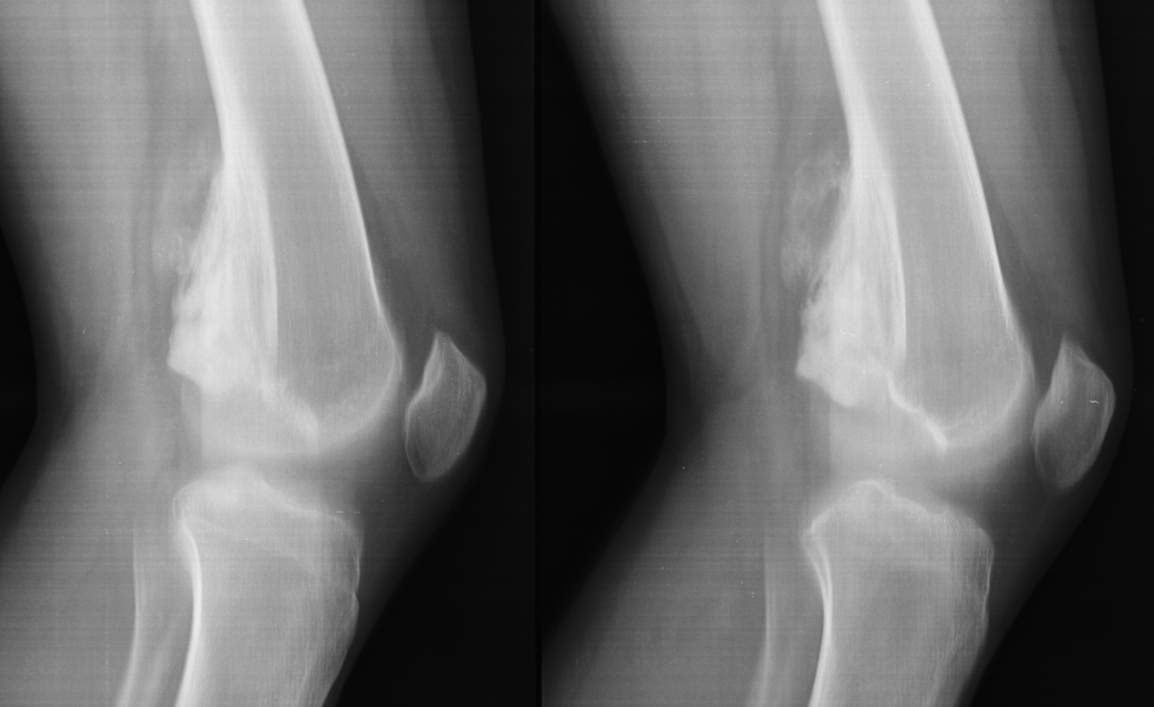

Остеосаркома коленного сустава: информация и поддержка